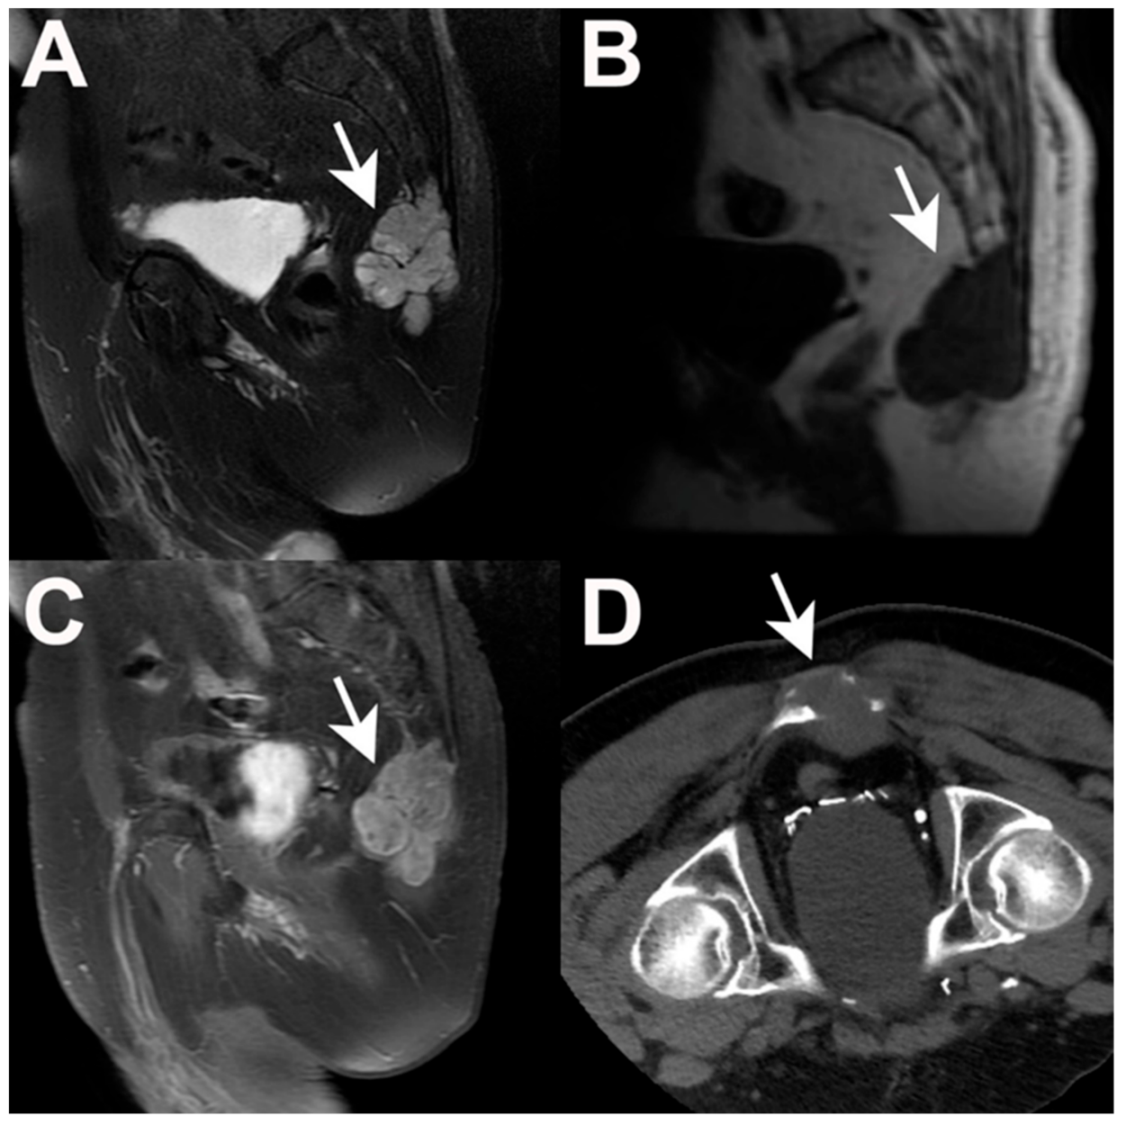

5.1. Imaging

- Disler, D.G.; Miklic, D. Imaging findings in tumors of the sacrum. Am. J. Roentgenol. 1999, 173, 1699–1706. [Google Scholar] [CrossRef]

- Farsad, K.; Kattapuram, S.V.; Sacknoff, R.; Ono, J.; Nielsen, G.P. Sacral Chordoma. RadioGraphics 2009, 29, 1525–1530. [Google Scholar] [CrossRef] [PubMed]